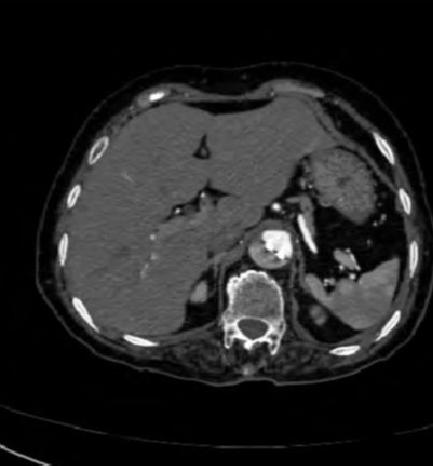

下面这个CT平扫,似乎有大问题!

图22

什么问题?似乎这里有大问题!

图23

同学,你眼神太好使了!

很可惜,这个不是问题,很多CT平扫都有这种线样阴影!

做个增强CT一看,哇,同学,你不光眼神好,运气也不是一般的好!

图24